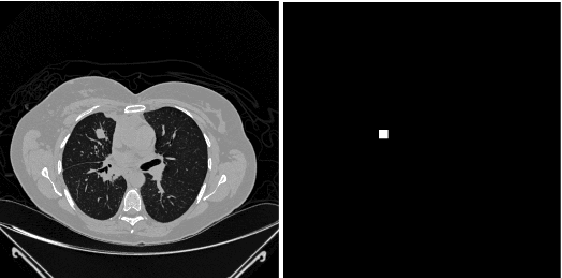

Abstract:Lung cancer is one of the most deadly diseases in the world. Detecting such tumors at an early stage can be a tedious task. Existing deep learning architecture for lung nodule identification used complex architecture with large number of parameters. This study developed a cascaded architecture which can accurately segment and classify the benign or malignant lung nodules on computed tomography (CT) images. The main contribution of this study is to introduce a segmentation network where the first stage trained on a public data set can help to recognize the images which included a nodule from any data set by means of transfer learning. And the segmentation of a nodule improves the second stage to classify the nodules into benign and malignant. The proposed architecture outperformed the conventional methods with an area under curve value of 95.67\%. The experimental results showed that the classification accuracy of 97.96\% of our proposed architecture outperformed other simple and complex architectures in classifying lung nodules for lung cancer detection.